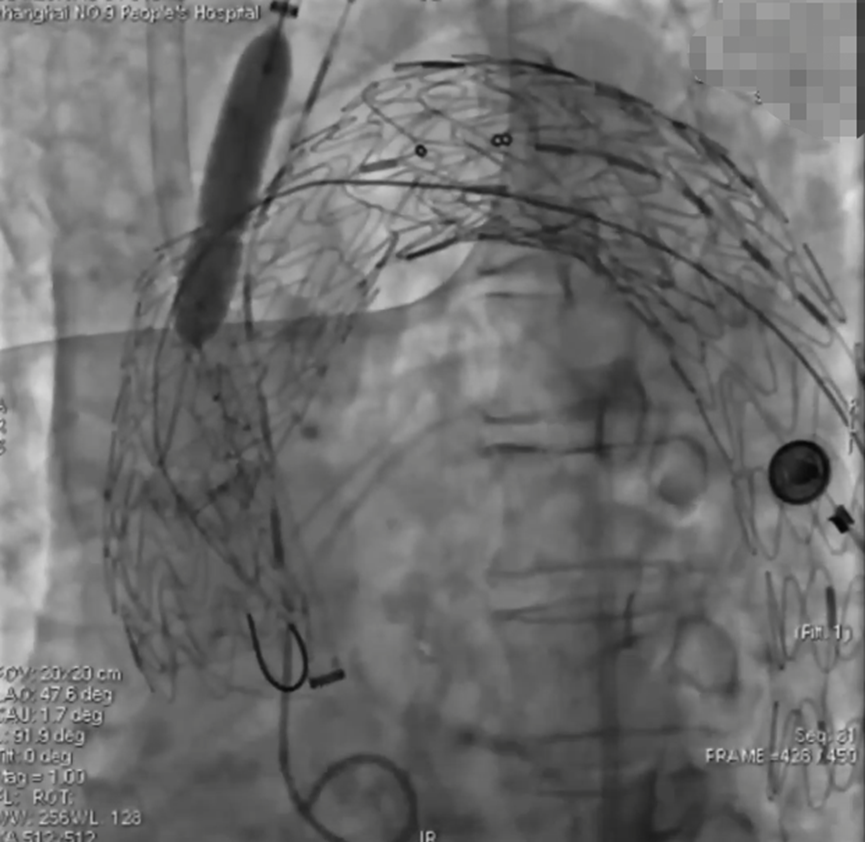

手术过程(四):回撤头臂干导管鞘,使其抵于戈尔支架表面,同样方法行激光原位开窗。开窗成功后,先前推进球囊,进入覆膜支架,交换硬导丝后行球囊扩张。植入覆膜支架,完成头臂干动脉重建。

波科支架怎么样陆信武:激光原位开窗重建弓上分支治疗A型主动脉夹层_https://www.jmylbn.com_新闻资讯_第7张

手术过程(四):自左肱动脉植入8F长鞘,抵至戈尔支架处,行左锁骨下动脉激光原位开窗。球囊扩张后,植入Lifestream覆膜支架。

波科支架怎么样陆信武:激光原位开窗重建弓上分支治疗A型主动脉夹层_https://www.jmylbn.com_新闻资讯_第8张